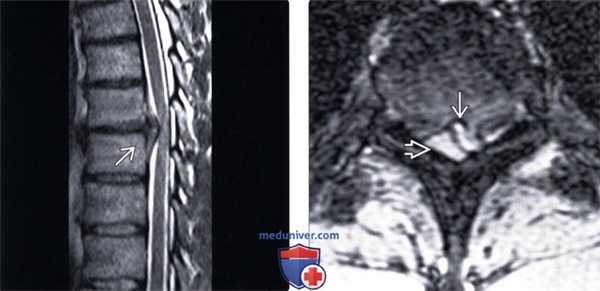

(Слева) Т2-ВИ, сагиттальный срез: крупная грыжа диска грудного отдела позвоночника, сдавливающая передний отдел спинного мозга. Края грыжи расположены наклонно и образованы задней продольной связкой и венами.

(Справа) На аксиальном Т2 *GRE верхнегрудного межпозвонкового диска видна крупная левосторонняя экструзия, сдавливающая левый боковой край спинного мозга.

(Слева) Т1-ВИ с КУ, сагиттальный срез: крупное гипоинтенсивное объемное образование, являющееся продолжением межпозвонкового диска и представляющее собой кальцифицированную экструзию диска. Расширенные эпидуральные вены окружают грыжу в виде тента.

(Справа) Т1-ВИ с КУ, аксиальный срез: крупная кальцифицированная экструзия грудного межпозвонкового диска, определяемая в виде гипоинтенсивного эпидурального образования, деформирующего спинной мозг.

(Слева) Т1-ВИ, сагиттальный срез: крупная грыжа грудного межпозвонкового диска на уровне Т10-Т11, мигрировавшая краниально на заднюю поверхность тела Т10. На уровнях Т10-Т11 и Т11-Т12 отмечается выраженная дегенерация дисков с формированием феномена вакуума.

(Справа) Т2-ВИ, сагиттальный срез: крупная экструзия межпозвонкового диска, определяемая в виде образования промежуточной интенсивности, мигрировавшая краниально на заднюю поверхность тела Т10 и представляющая здесь собой свободный фрагмент.